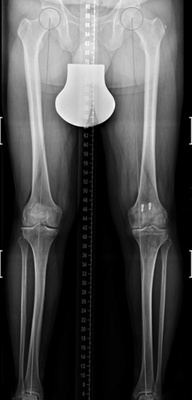

Dr. med. Alexander Strehl: Bei einer Umstellungsosteotomie wird die Lastachse im Knie und somit auch auf den Knorpel korrigiert. Korrekterweise geht die Belastung vom Oberschenkelkopfzentrum zum Sprunggelenkszentrum etwa mittig durchs Knie. Bei O- oder X-Beinen weicht diese Achse ab. Dies kann aus unterschiedlichen Gründen sein, zum Beispiel durch einen früheren Beinbruch oder weil der Patient in der Zeit des Skelettwachstums viel Fussball gespielt hat, kommt aber auch oft ohne eigentliche Ursache vor. Das O-Bein ist häufiger als das X-Bein. Manchmal sieht man diese Abweichung der Beinachse nicht auf den ersten Blick, sondern erst mit einer Ganzbeinstandaufnahme.

Durch O- oder X-Beine wird der Knorpel im Knie einseitig belastet. Da reichen manchmal schon wenige Millimeter, die die Achse abweicht. Folge ist, dass sich eine Knorpelseite deutlich schneller abnutzt als die andere. Mit der Operation wird die Belastung zurück auf die Mitte gesetzt oder eine kleine Überkorrektur auf die gesunde Seite vollzogen, sodass diese etwas mehr belastet und die abgenutztere Seite entlastet wird.